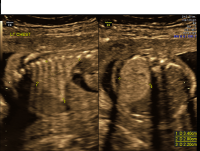

Congenital Cystic Adenomatoid Malformation (CCAM)

CCAM

Pregnancies with CCAM are followed closely with ultrasound to monitor the size of the lesion and ensure continued fetal well-being. Magnetic resonance imaging (MRI) is also recommended to better define these lesions, and fetal echocardiography is also performed to exclude associated heart problems. Consultations with neonatology and pediatric surgery are recommended to discuss prognosis and management after birth. While most CCAMs are well-tolerated during pregnancy, large CCAMs may lead to significant complications and must be watched closely.